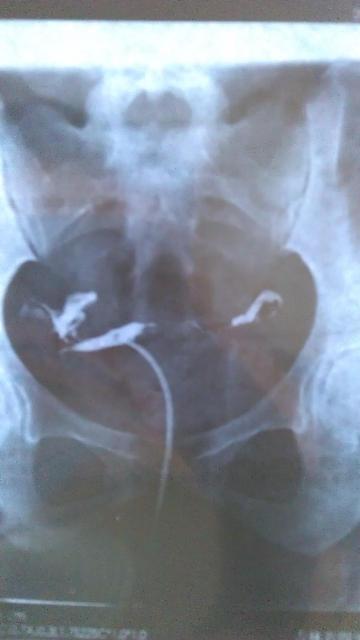

患者信息:女 28岁 病情描述(发病时间、主要症状等):表现:注入造影剂后,宫腔充盈,子宫影大致呈三角形位置偏左,边缘光滑。两宫角充盈可, 双侧输卵管在宫旁连续显示,边缘光滑,造影剂经双侧伞端溢入盆腔,并可见少许弥散。第三张片显示盆腔内见有游离造影剂。诊断:子宫影显示正常,双侧输卵管通畅。 本人月经正常,周期27-28天,卵泡监测排卵正常,大小在2.0*1.9左右想得到怎样的帮助:结婚一年一直没有宝宝,去医院做造影后说我盆内输卵管有粘连,医生让我住院治疗两个疗程,我只住院治疗一个疗程,这个月不想去了,我找人说先让我先吃两瓶八珍益母丸,请问看片子我是否还要住院?我是否可以要宝宝了曾经治疗情况及是否有过敏、遗传病史:无